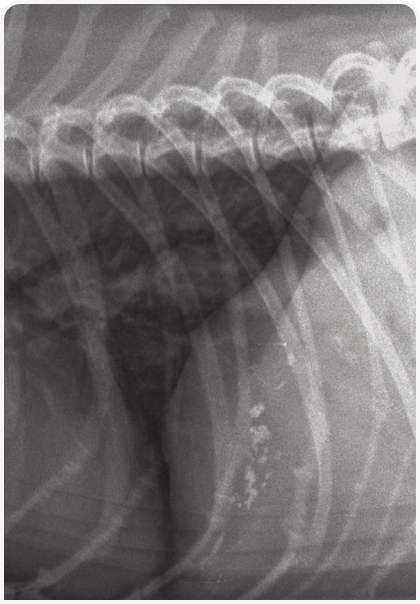

Рентгенография позволяет оценить размеры и контуры печени, но не изменения паренхимы (кроме скопления газов или минерализации). Для исследования нужно получить изображения брюшной полости на выдохе в двух ортогональных проекциях (боковой и вентродорсальной). Чтобы полностью визуализировать печень, важно включить в рентгенограмму брюшной полости краниальный край диафрагмы.

Силуэт печени невозможно отличить от диафрагмы, а каудально он ограничен желудком. Каудовентральный край нормальной печени острый (Рисунок 1). Оценивать размеры печени удобнее по желудочной оси; на боковой рентгенограмме печень должна быть видна между линией, проведенной под углом 90 градусов к позвоночнику, и линией, параллельной последней паре ребер. Если ось желудка смещена за пределы последней пары ребер или если каудальный край печени простирается до вентральной части желудка, это указывает на гепатомегалию. Если желудок смещен краниально, печень, по всей вероятности, маленькая, хотя такое явление в норме встречается у собак с глубокой грудной клеткой, таких как боксер, доберман, немецкий дог. При заболеваниях печени часто развивается асцит (скопление жидкости в брюшной полости), который в некоторых случаях может затруднять обследование печени. Однако асцит легко распознать на рентгенограммах брюшной полости по снижению четкости серозной оболочки, а в тяжелых случаях – по отвислому животу.

В норме желчный пузырь на рентгеновском снимке не виден. Однако иногда у кошек вентральная часть желчного пузыря может распространяться за пределы вентрального края контура печени на серповидную жировую подушку (falciform fat); ее следует дифференцировать с объемными образованиями. Желчнокаменная болезнь часто вызывает минерализацию ткани печени, а при поражении внутрипеченочных желчных протоков на рентгенограмме появляются ветвистые тени (Рисунок 2).